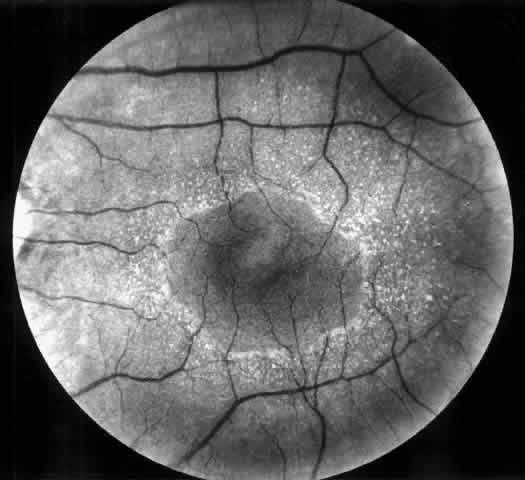

Drusen-like lesions and retinal pigment epithelium damage have also been recognized as a feature of MPGN type II.72–79 In a fluorescein angiographic study of 26 patients who had biopsy-proven MPGN type II, specific fundus lesions were identified in 24 patients (92%).79 Two adolescents with a history of renal disease of 13 months and 2 months had normal fundi. Small-sized lesions similar to small hard drusen were observed in all 24 patients with a history of renal disease lasting for 16 months or more (Fig. 6). In all 15 subjects with a history of renal disease of at least 12 years, larger drusen-like lesions were also noticed. In all 11 patients with renal disease persisting for 18 years or more, drusen occupied most of the fundus and areas of geographic atrophy were seen as well. Foci of new vessels and disciform scarring were observed in eight eyes of five patients with a renal history of 15 years or more (Fig. 7). Most eyes that did not show subretinal neovascularization had normal or nearly normal vision and visual fields. Three patients, however, exhibited ocular symptoms, which were related to pronounced macular atrophic changes, hypertensive retinopathy, and cataracts. The type of fundus lesions was statistically correlated (p<0.0001) with the duration of the renal disease, but not with age, sex, or renal insufficiency. Fundus changes between first and last visit as well as cross-sectional studies suggest a slow progression of retinal disease, which is probably independent of treatment and age of the patient.77–79

Fig. 7. Fluorescein angiographic changes in a 32-year-old patient with renal signs of membranoproliferative glomerulonephritis type II since the age of 9 years. Numerous small and larger drusen-like lesions, atrophic changes, and a small infrafoveolar subretinal neovascular membrane that was successfully treated with argon laser coagulation can be seen. (Leys A, Michielsen B, Leys M et al: Subretinal neovascular membranes associated with chronic membranoproliferative glomerulonephritis type II. Graefes Arch Clin Exp Ophthalmol 228:499, 1990)